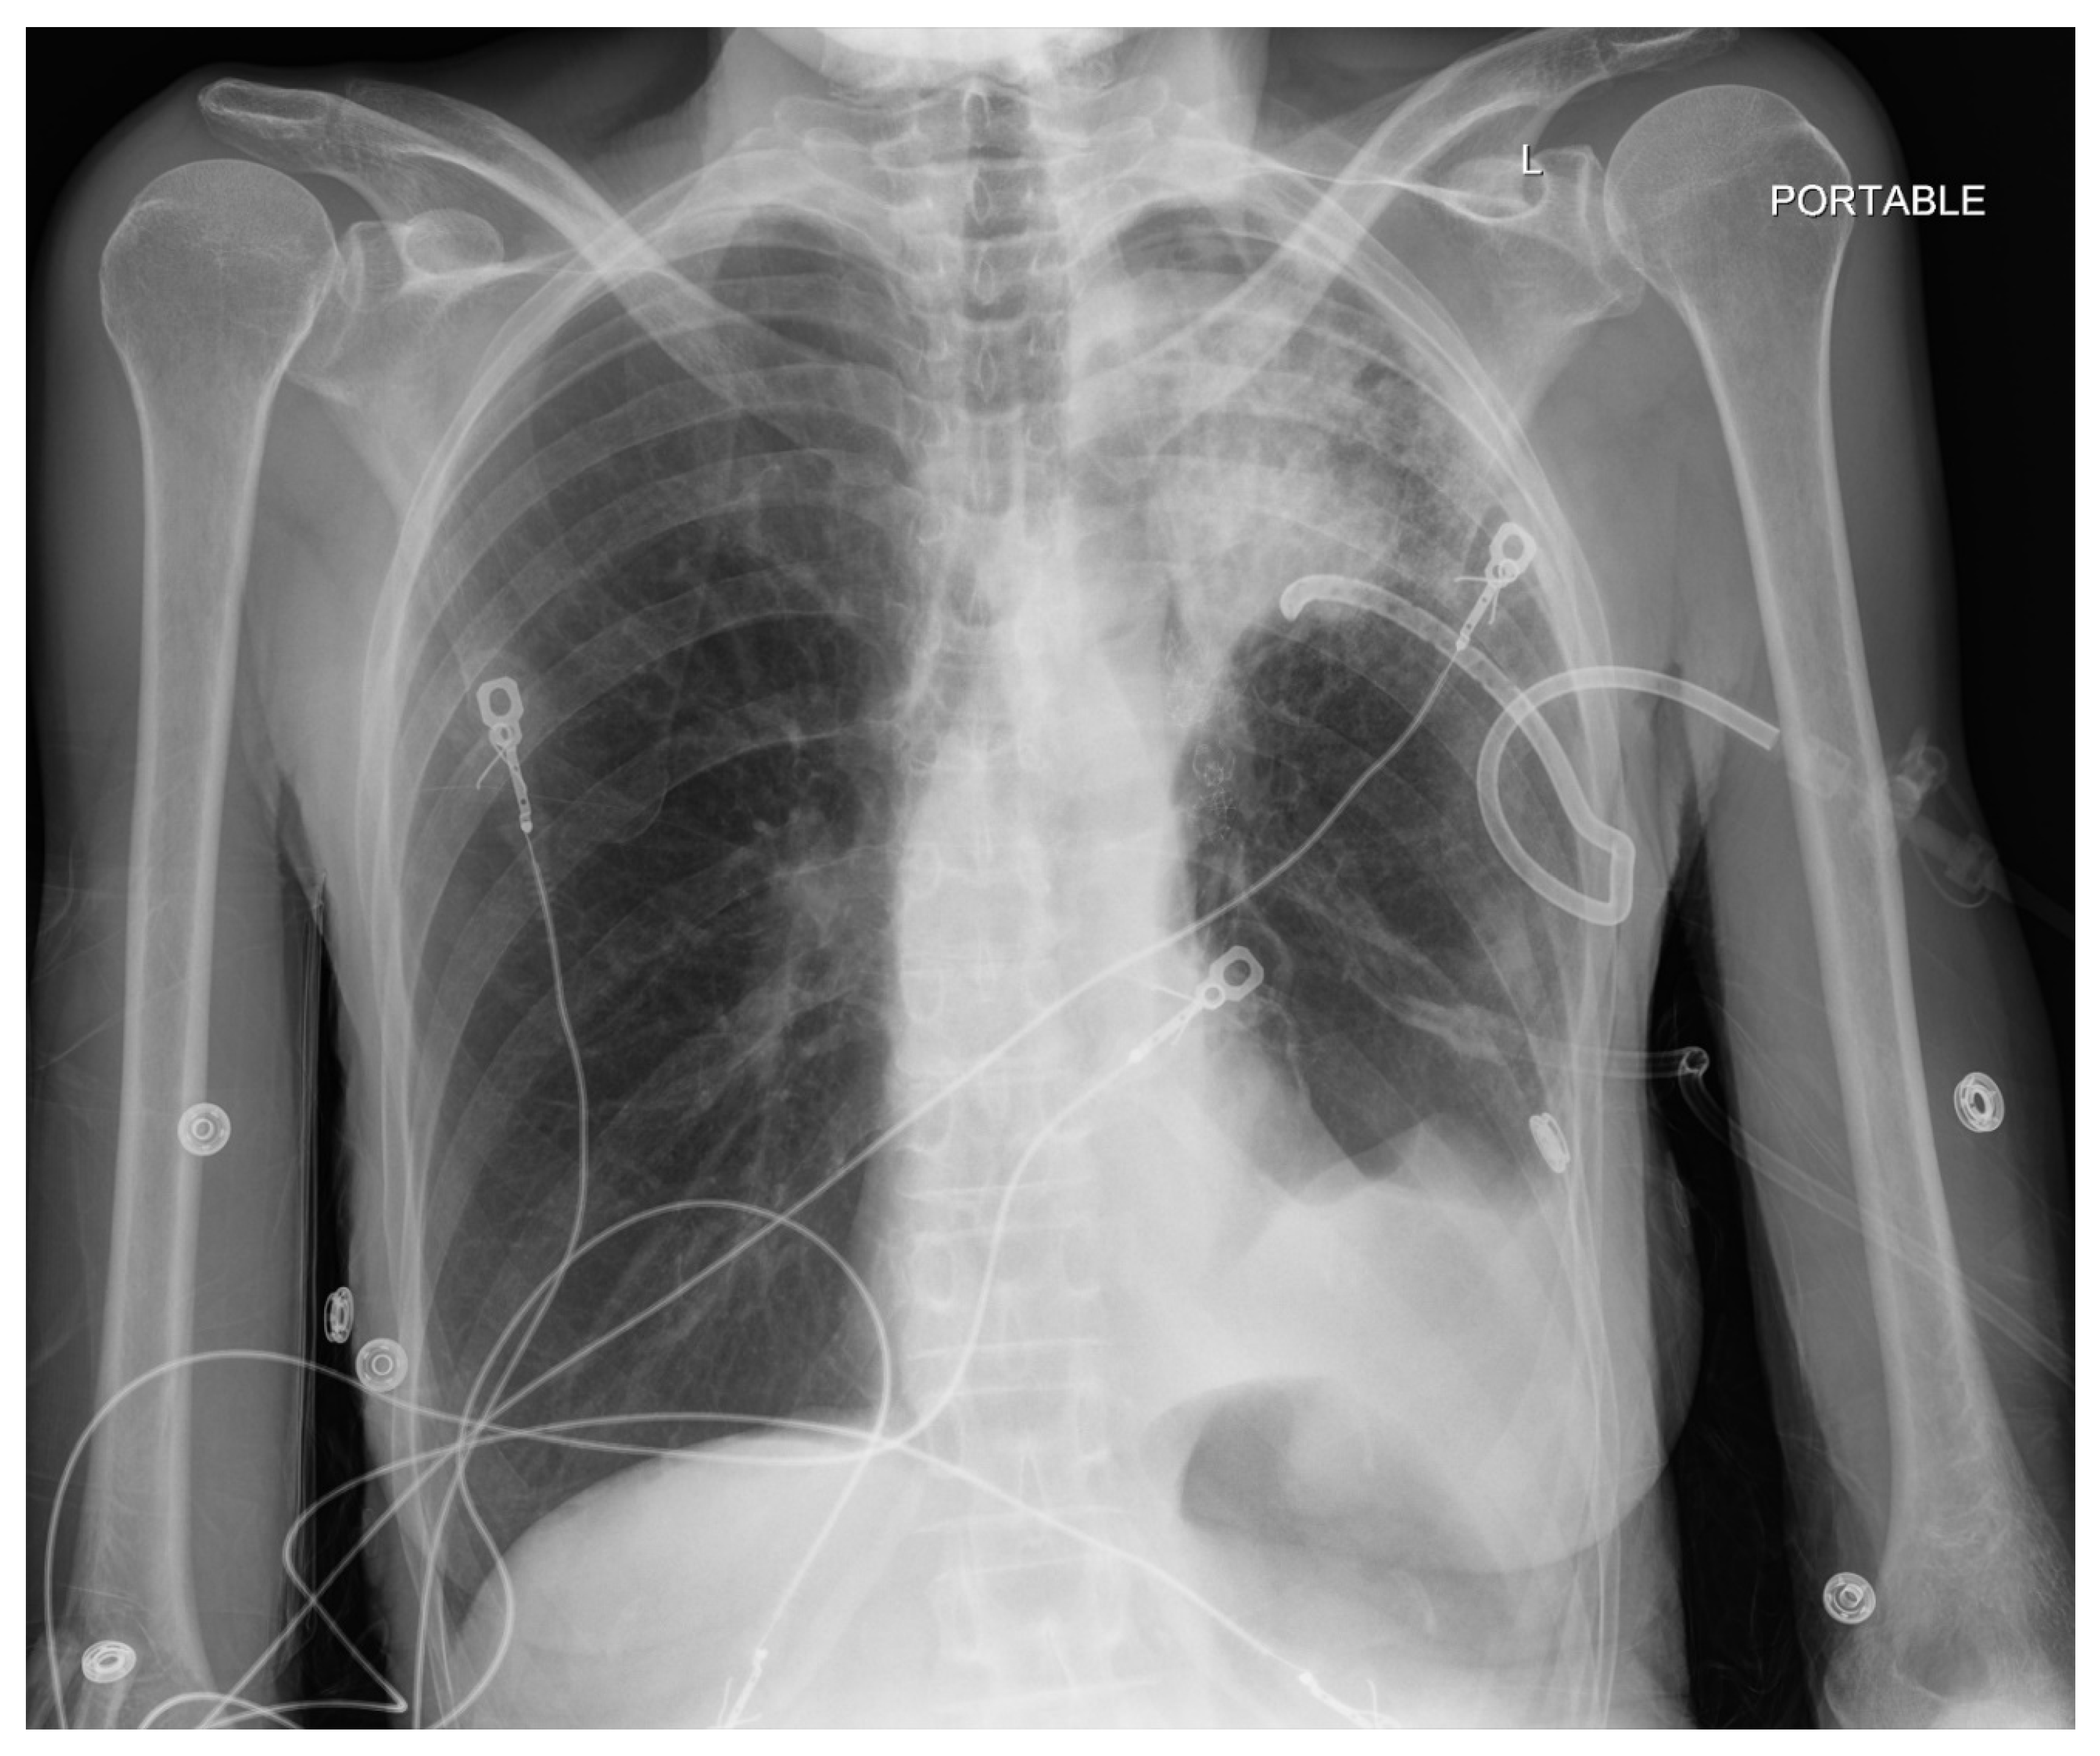

Pneumothorax (Figure 1, Figure 2, Figure 3 and Figure 4) developing after the placement of endobronchial valve (Figure 5) is usually managed by pulmonologists; however, anesthesia providers should be aware. Dijk et al. published their revised expert statement that addresses the issue of pneumothorax extensively [53]. The development of pneumothorax is related to compensatory expansion of the untreated ipsilateral lobe. Such an expansion might result in the rupture of blebs, bullae, and fragile lung tissue [54]. The bronchopleural fistula that develops leads to air leak, which can get worse and become clinically significant very quickly. Pneumothorax can also develop in the vacuum created by therapeutic lung collapse (pneumothorax ex vacuo). The air enters the potential space from the ambient tissues and blood [55]. As there is no bronchoalveolar fistula in this situation, a chest drain is not necessary, and the pneumothorax will spontaneously resolve over time.

Pneumothorax can develop in the immediate postoperative period, in the post anesthesia care unit or within the first 3 days [46,56]. Valipou et al. published their management algorithm for pneumothorax [57]. Nearly 80% of them happen in the first 48 h, 10% in about 3-5 days, and 10% after day 6 [58,59]. Both anesthesia providers and bronchoscopists should be particularly vigilant about the development of tension pneumothorax. Certain post procedural protocols- (cough suppression, strict bed rest, not letting to elevate the arm above shoulders) are employed at Jefferson to minimize the pneumothorax risk. Most pneumothoraces ‘s are treated conservatively with serial imaging. some may require chest tubes and rarely valve removal.

Figure 1. Pre-procedure Chest X-ray (CXR) Pt is a former smoker-who smoked 3 cigarettes a day for 15 years, quit 20 years ago, with severe COPD deemed suitable for bronch valve.

Figure 2. CXR, taken about 16 hours after placement of bronchial valve, Large left pneumothorax with rightward mediastinal shift. Left basilar atelectasis.